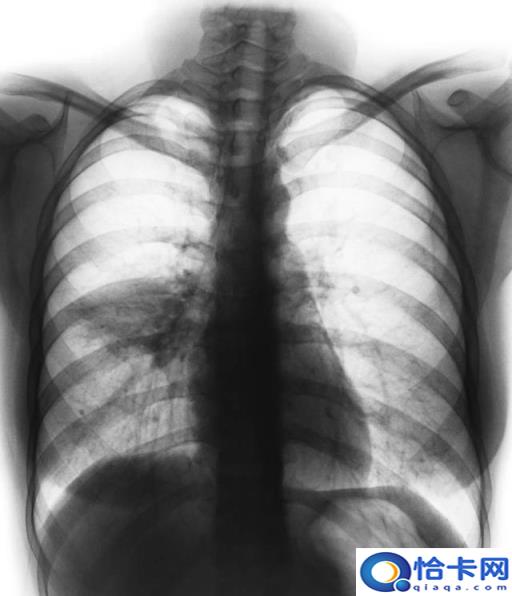

二、收集呼吸道标本

对于NCP疑似患者无法通过临床表现和肺部影像学准确区分患者是新型冠状病毒感染还是其他常见呼吸道病毒感染。诊断应采集鼻咽或口咽拭子、痰、支气管分泌物、支气管肺泡灌洗液样本,提取样本中核酸,实时荧光定量逆转录聚合酶链反应(RT-PCR)检测新型冠状病毒核酸或病毒基因测序[1],达到疫情防控的早期诊断、早期发现、早期治疗、早期隔离的目的。新型冠状病毒具有很强的传染性。在呼吸道标本采集过程中,既有普通病原体标本采集的共同点,也有甲类传染病防治的特殊点。对NCP收集呼吸道标本的建议如下。